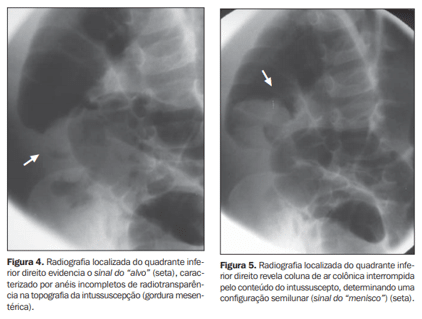

Entre os principais achados ultrassonográficos, destacam-se:

- Sinal do alvo (target sign): visualizado em cortes transversais, caracteriza-se por múltiplos anéis concêntricos com hiperecogenicidade periférica e centro hipoecogênico.

- Sinal do pseudorrim: observado em cortes longitudinais, lembra um rim, com camadas intestinais invaginadas simulando o parênquima e a pelve renal.